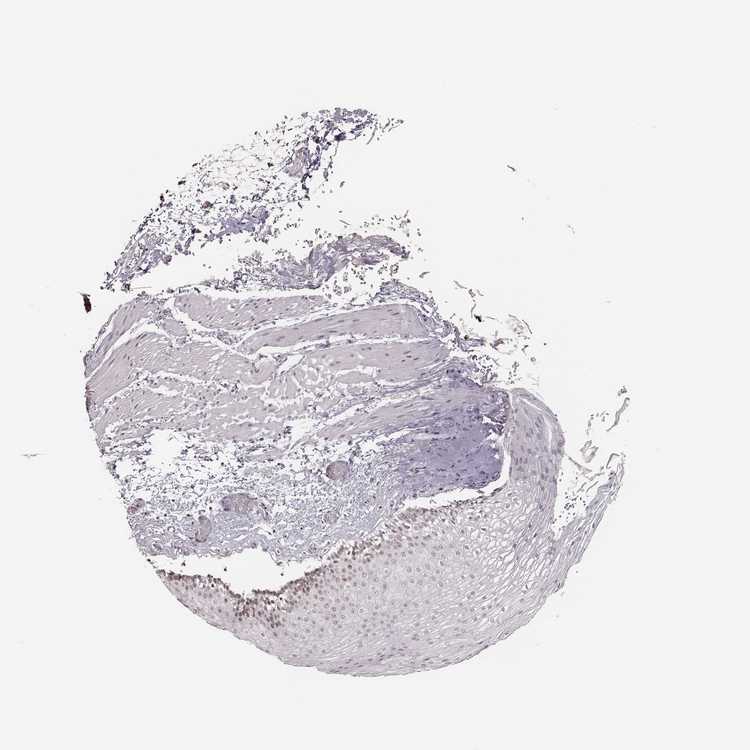

ESOPHAGUS - Antibody stainingi

Antibody staining in the annotated cell types in the current human tissue is reported as not detected, low, medium, or high, based on conventional immunohistochemistry profiling in selected tissues. This score is based on the combination of the staining intensity and fraction of stained cells.

Each image is clickable and will lead to virtual microscopy that enables deeper exploration of all samples and also displays staining intensity scores, fraction scores and subcellular localization as well as patient and tissue information for each sample.

Antibody HPA045168Antibody CAB000147Antibody CAB003839Antibody CAB003840Antibody CAB075726Antibody CAB075727

Squamous epithelial cells HighNot detectedNot detectedMediumMediumHigh